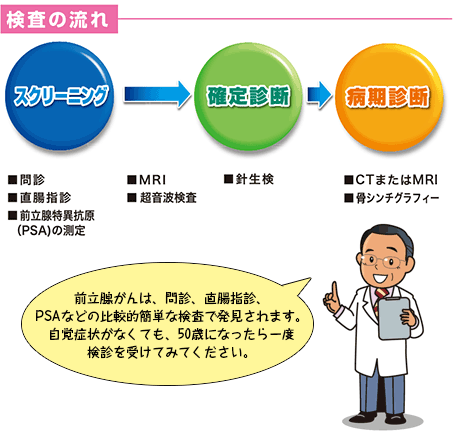

検査の流れ 50歳を過ぎたら注意 前立腺がん 患者 ご家族の皆様

確定診断までの流れ がんの治療法 詳しく知りたい 前立腺がん

確定診断までの流れ がんの治療法 詳しく知りたい 前立腺がん